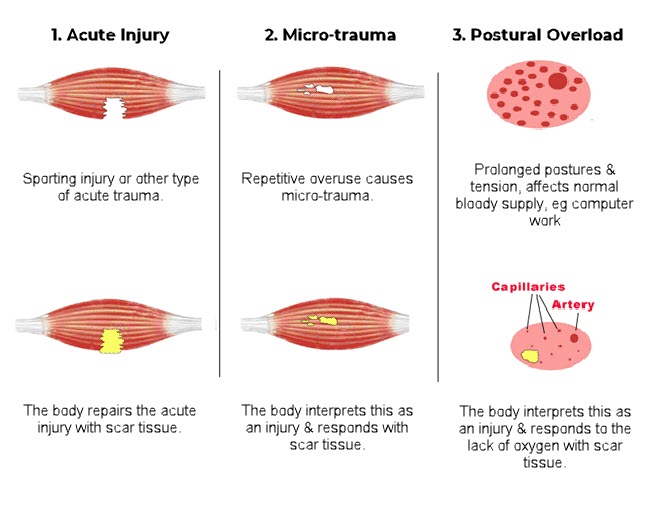

Ask The Doc What Is Soft Tissue Why Does It Matter

Ask The Doc What Is Soft Tissue Why Does It Matter